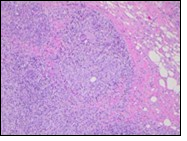

Core needle biopsy of idiopathic granulomatous mastitis enunciates multiple aggregates of non- caseating epitheloid cell granulomas within and encompassing breast lobules, constituted of epitheloid histiocytes, lymphocytes, neutrophils and multinucleated giant cells. Granulomatous inflammation is predominantly lobulo-centric. The inflammation is preponderantly composed of lymphocytes, plasma cells, epitheloid histiocytes, multinucleated giant cells and neutrophils. Neutrophils can configure micro-abscesses and encompass vacant micro-cystic cavities, morphological features which are in common with cystic neutrophilic granulomatous mastitis. Non specific lobulitis along with a lymphoid and plasma cell infiltrate accompanies the granulomatous inflammation. Necrosis is usually absent. Neutrophilic micro-abscesses can be accompanied by fistula formation 4, 5.

Multinucleated giant cells are detected in an estimated three fourths (78.5%) instances. Plasma cells are discernible in around half (53.9%) of the subjects and usually appear at the margins of cystic vacuoles with centric accumulation of neutrophils within the granulomas.

Figure 2.Granulomatous mastitis with articulated epitheloid cell granuloma, lymphocytic, plasma cell and neutrophilic infiltration10.